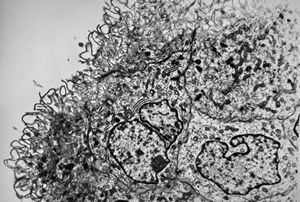

M,10y. | herpetic encephalitis